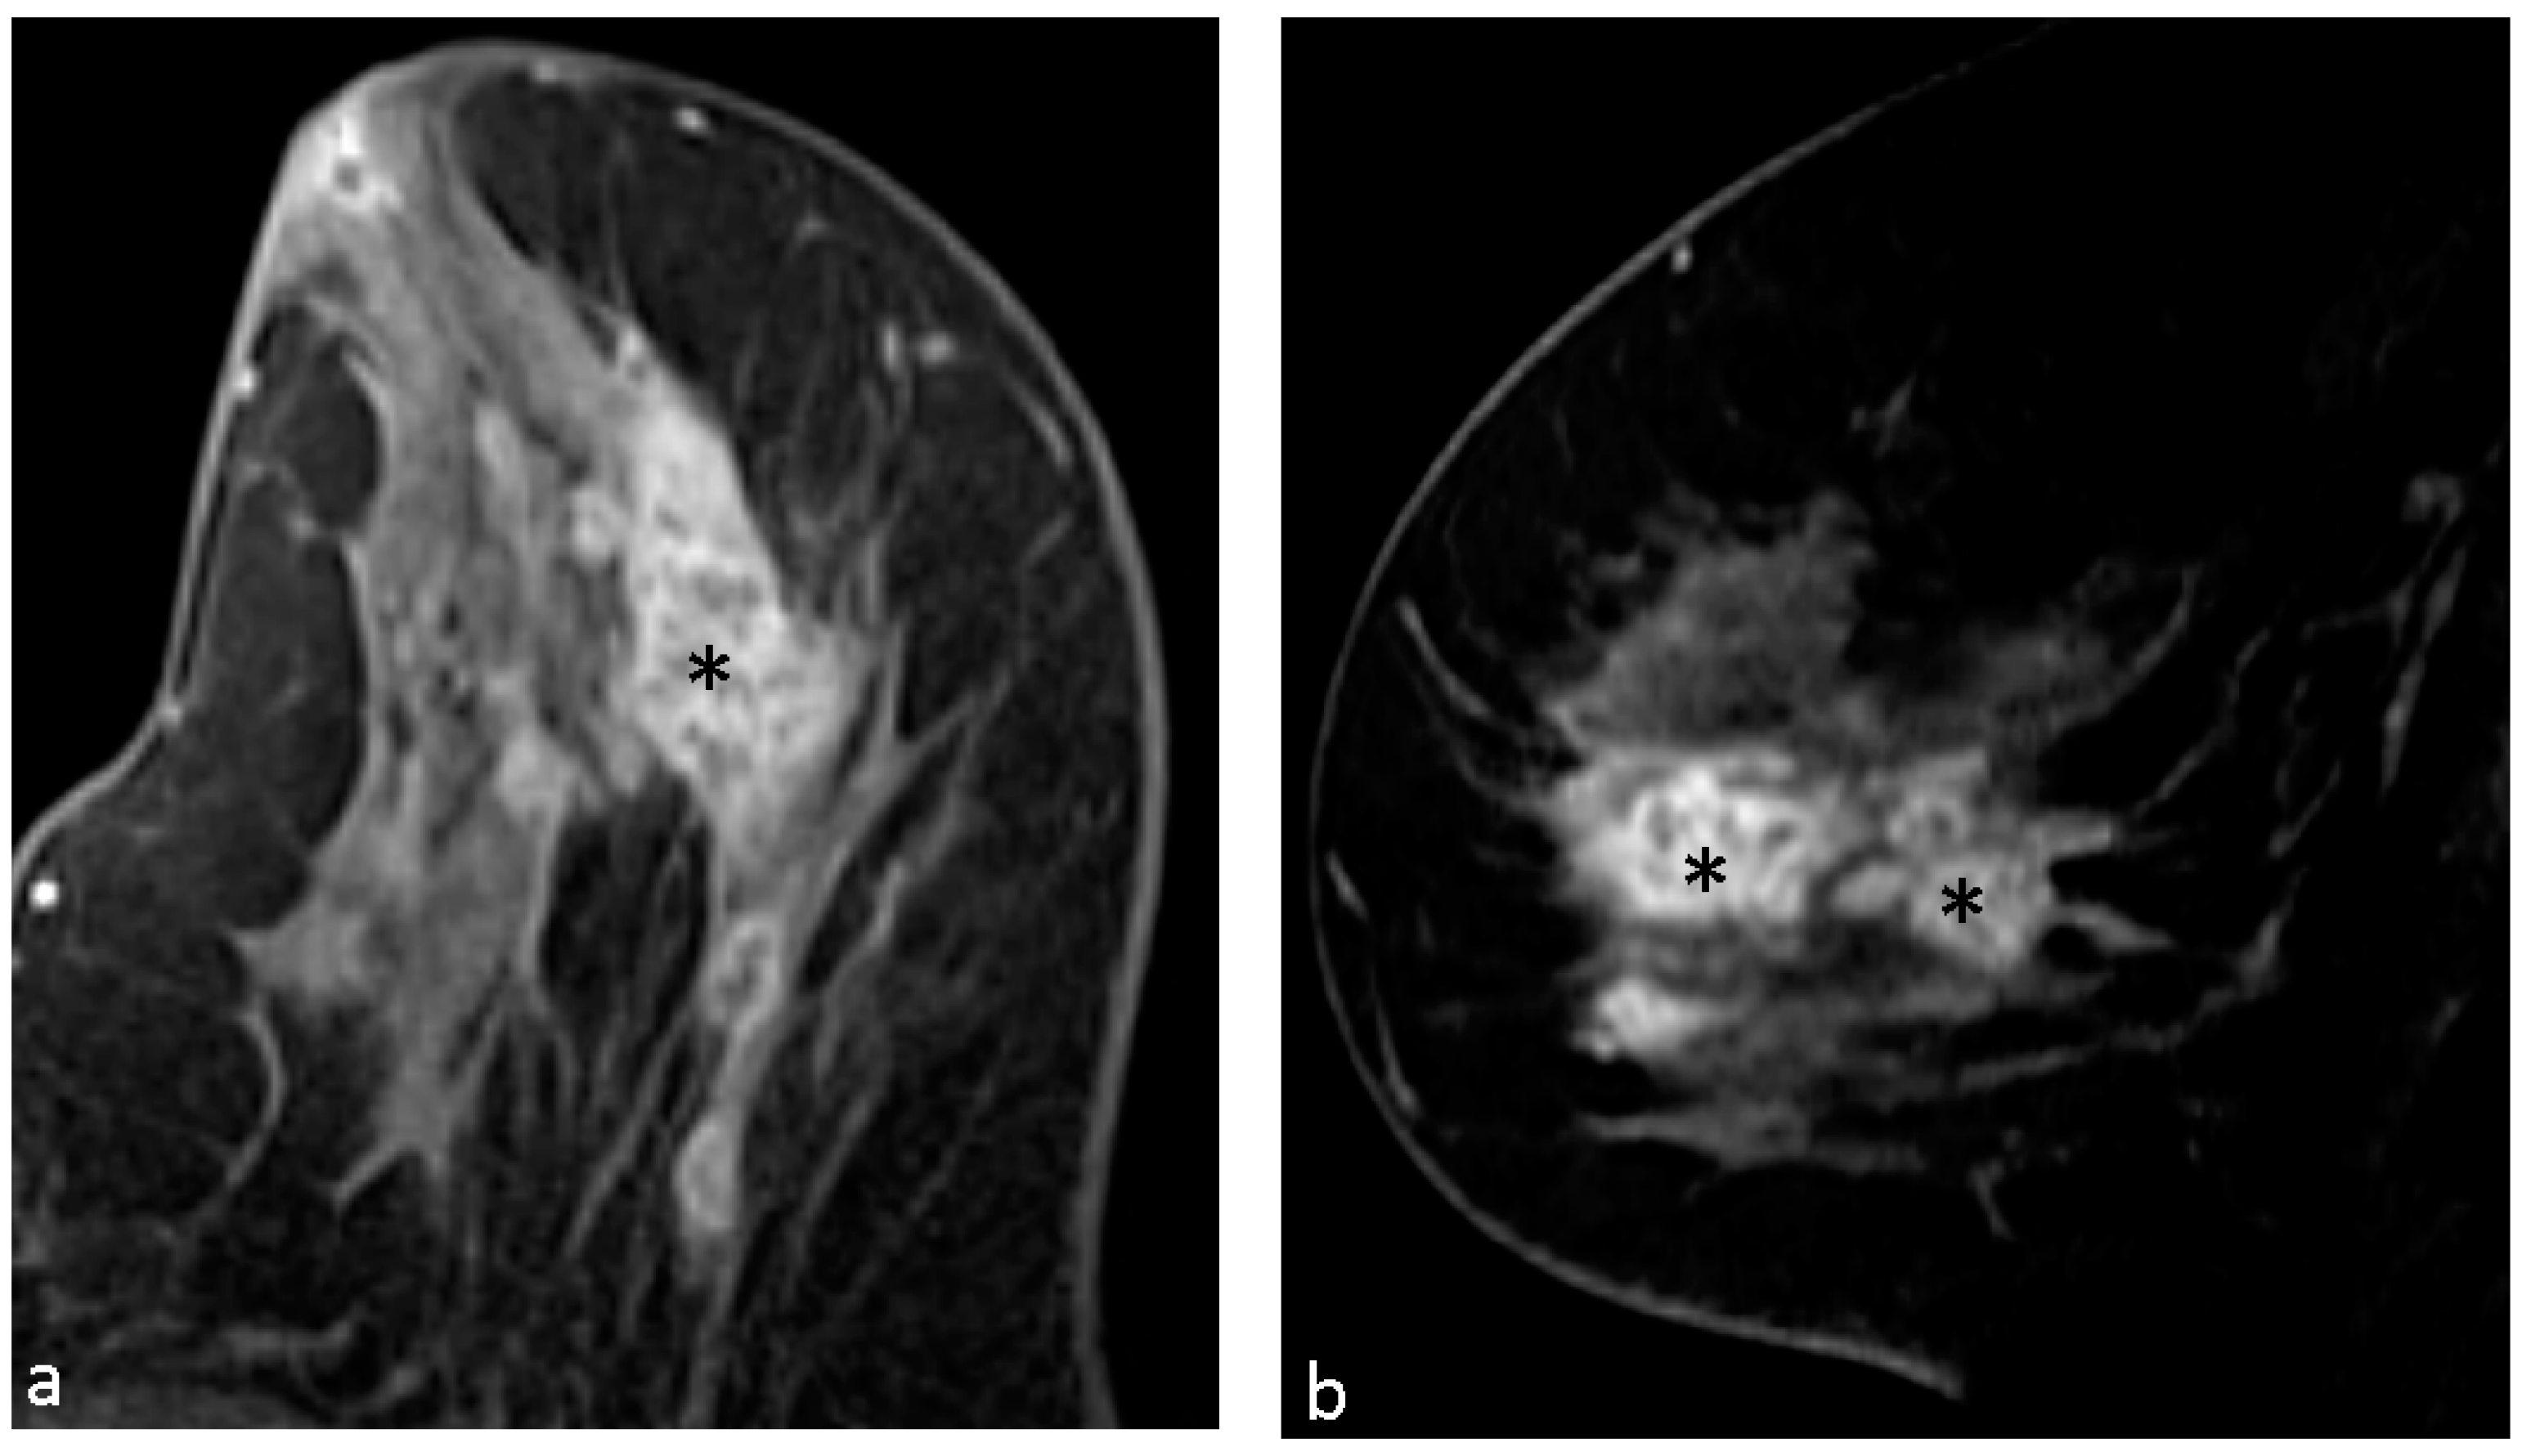

| Clustered ring enhancement | 31 (53.4%) |